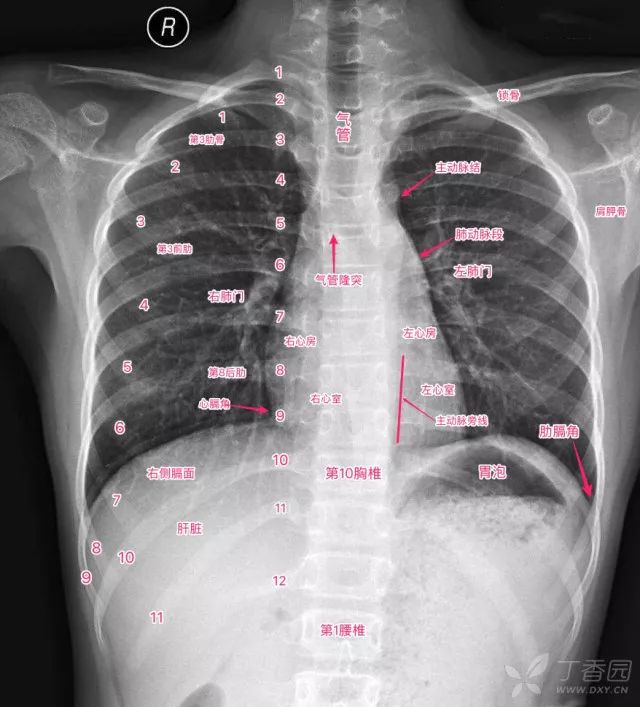

超详细胸片教学,不信你还学不会!

一张经典的胸片